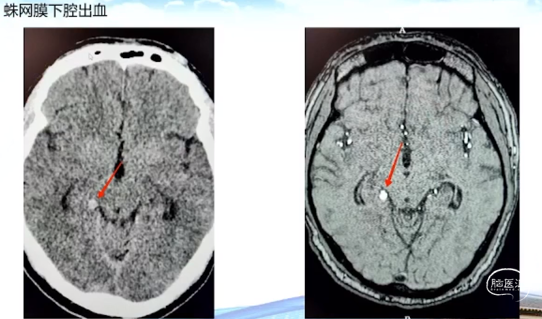

1.蛛网膜下腔出血

头颅CT检查:右侧环池区类圆形稍高密度结节(似与小脑幕相连),脑膜瘤?其他?(建议做MRI增强检查)大脑镰前份颗粒状钙化灶;左侧蝶窦、双侧筛窦少许炎症。

术前CT和MRI影像